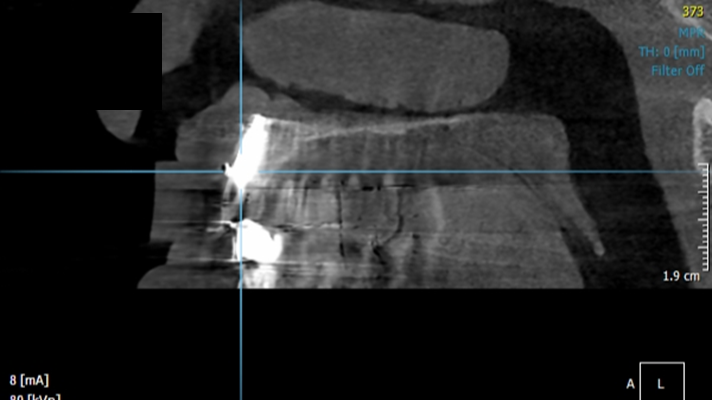

Clinical case: Peri-implantitis treatment case using titanium or NiTi brush

- Courtesy of Dr. Dae-Hee Lee, South Korea -

Dr. Dae-Hee Lee,Maxillary Anterior,Peri-implantitis,Bone regeneration,Aesthetic zone,#21,#22,GBR,Titanium Brush Set